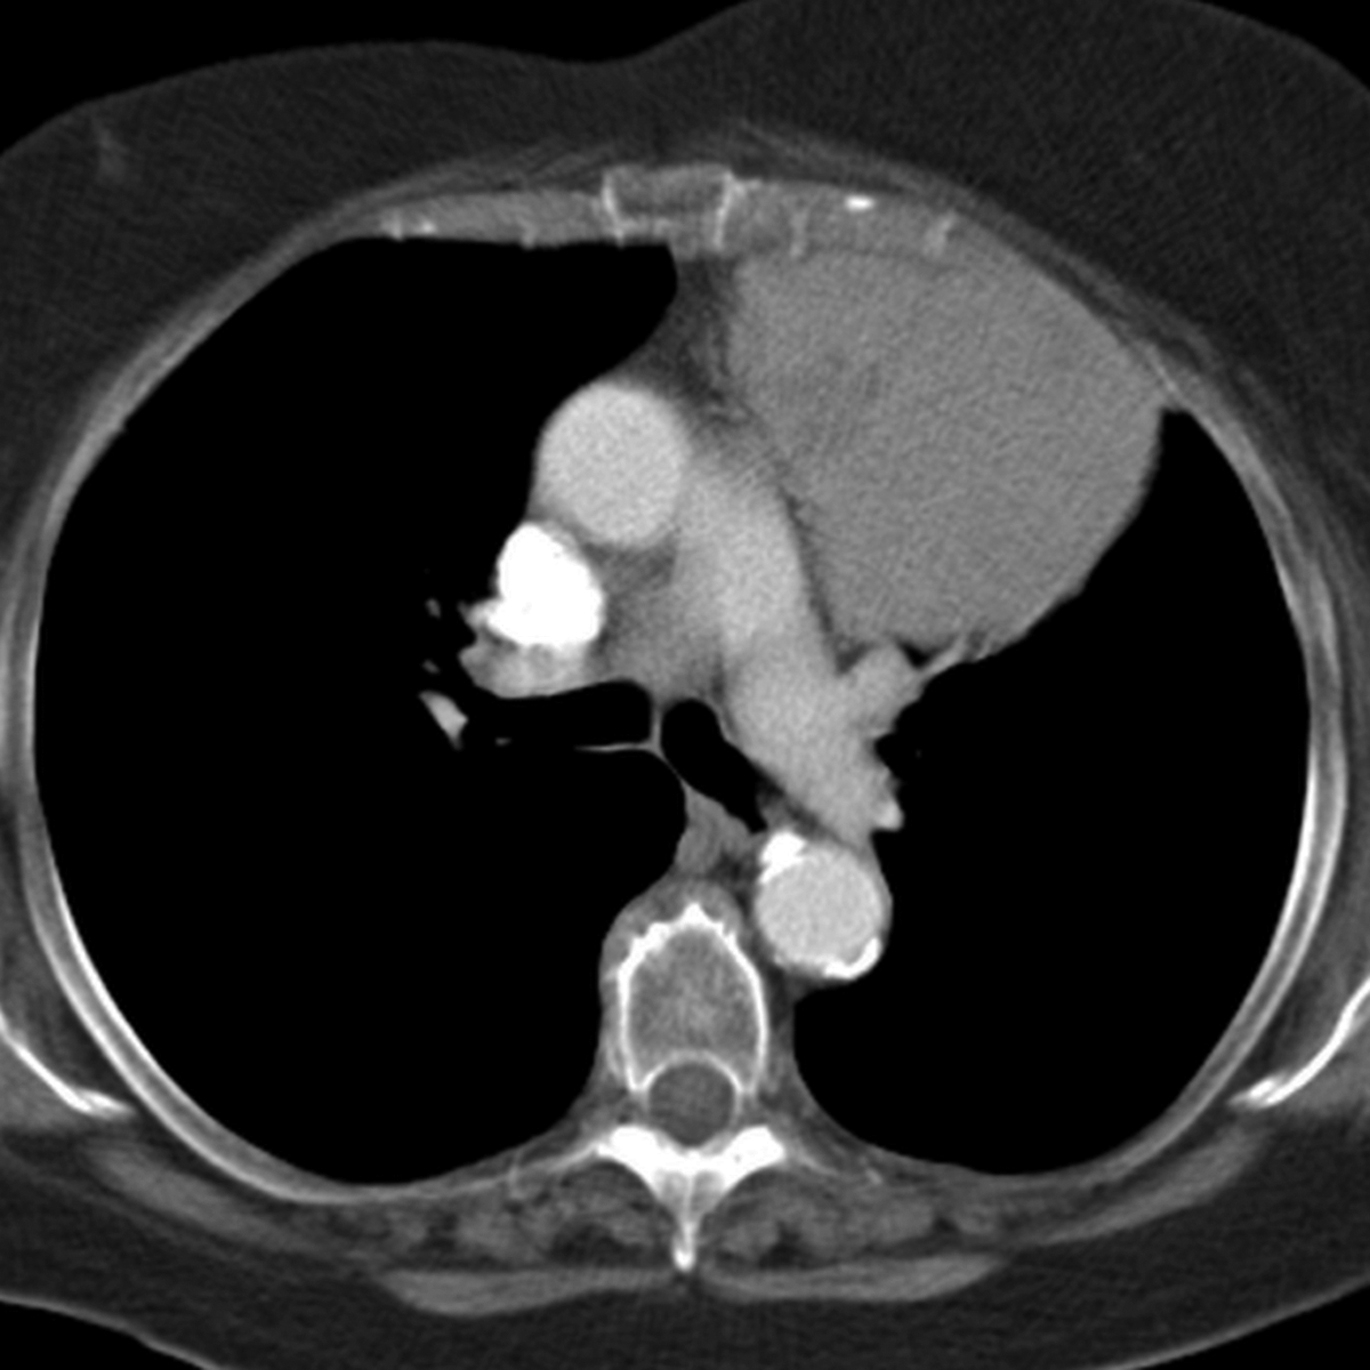

From radiologykey.com

The Acute Neck Inflammation, Infections, and Trauma Radiology Key Danger Space Mediastinum The danger space lies behind the true retropharyngeal space, and courses more inferiorly than the true retropharyngeal space, running into the posterior mediastinum until the level of. The danger space (alar space) is a deep compartment of the head and neck located posterior to the retropharyngeal space and. Inferiorly, the danger space is in free communication with the posterior mediastinum,. Danger Space Mediastinum.